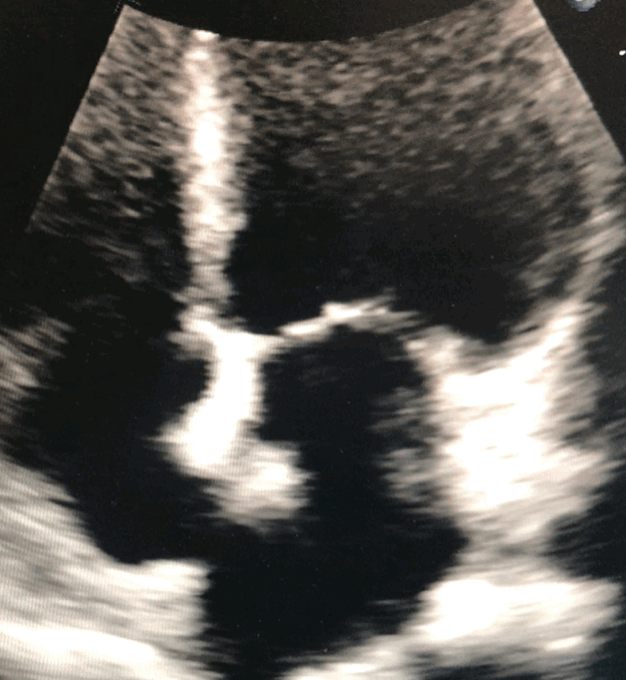

Echocardiography

Also known as echo, or trans-thoracic echo, an echocardiogram uses ultrasound waves to image the heart. The test takes around 40 minutes requires an ultrasound probe and gel to be placed on several locations around your chest. This test provides information on heart size and function. It allows assessment of the valves and flows within the heart.